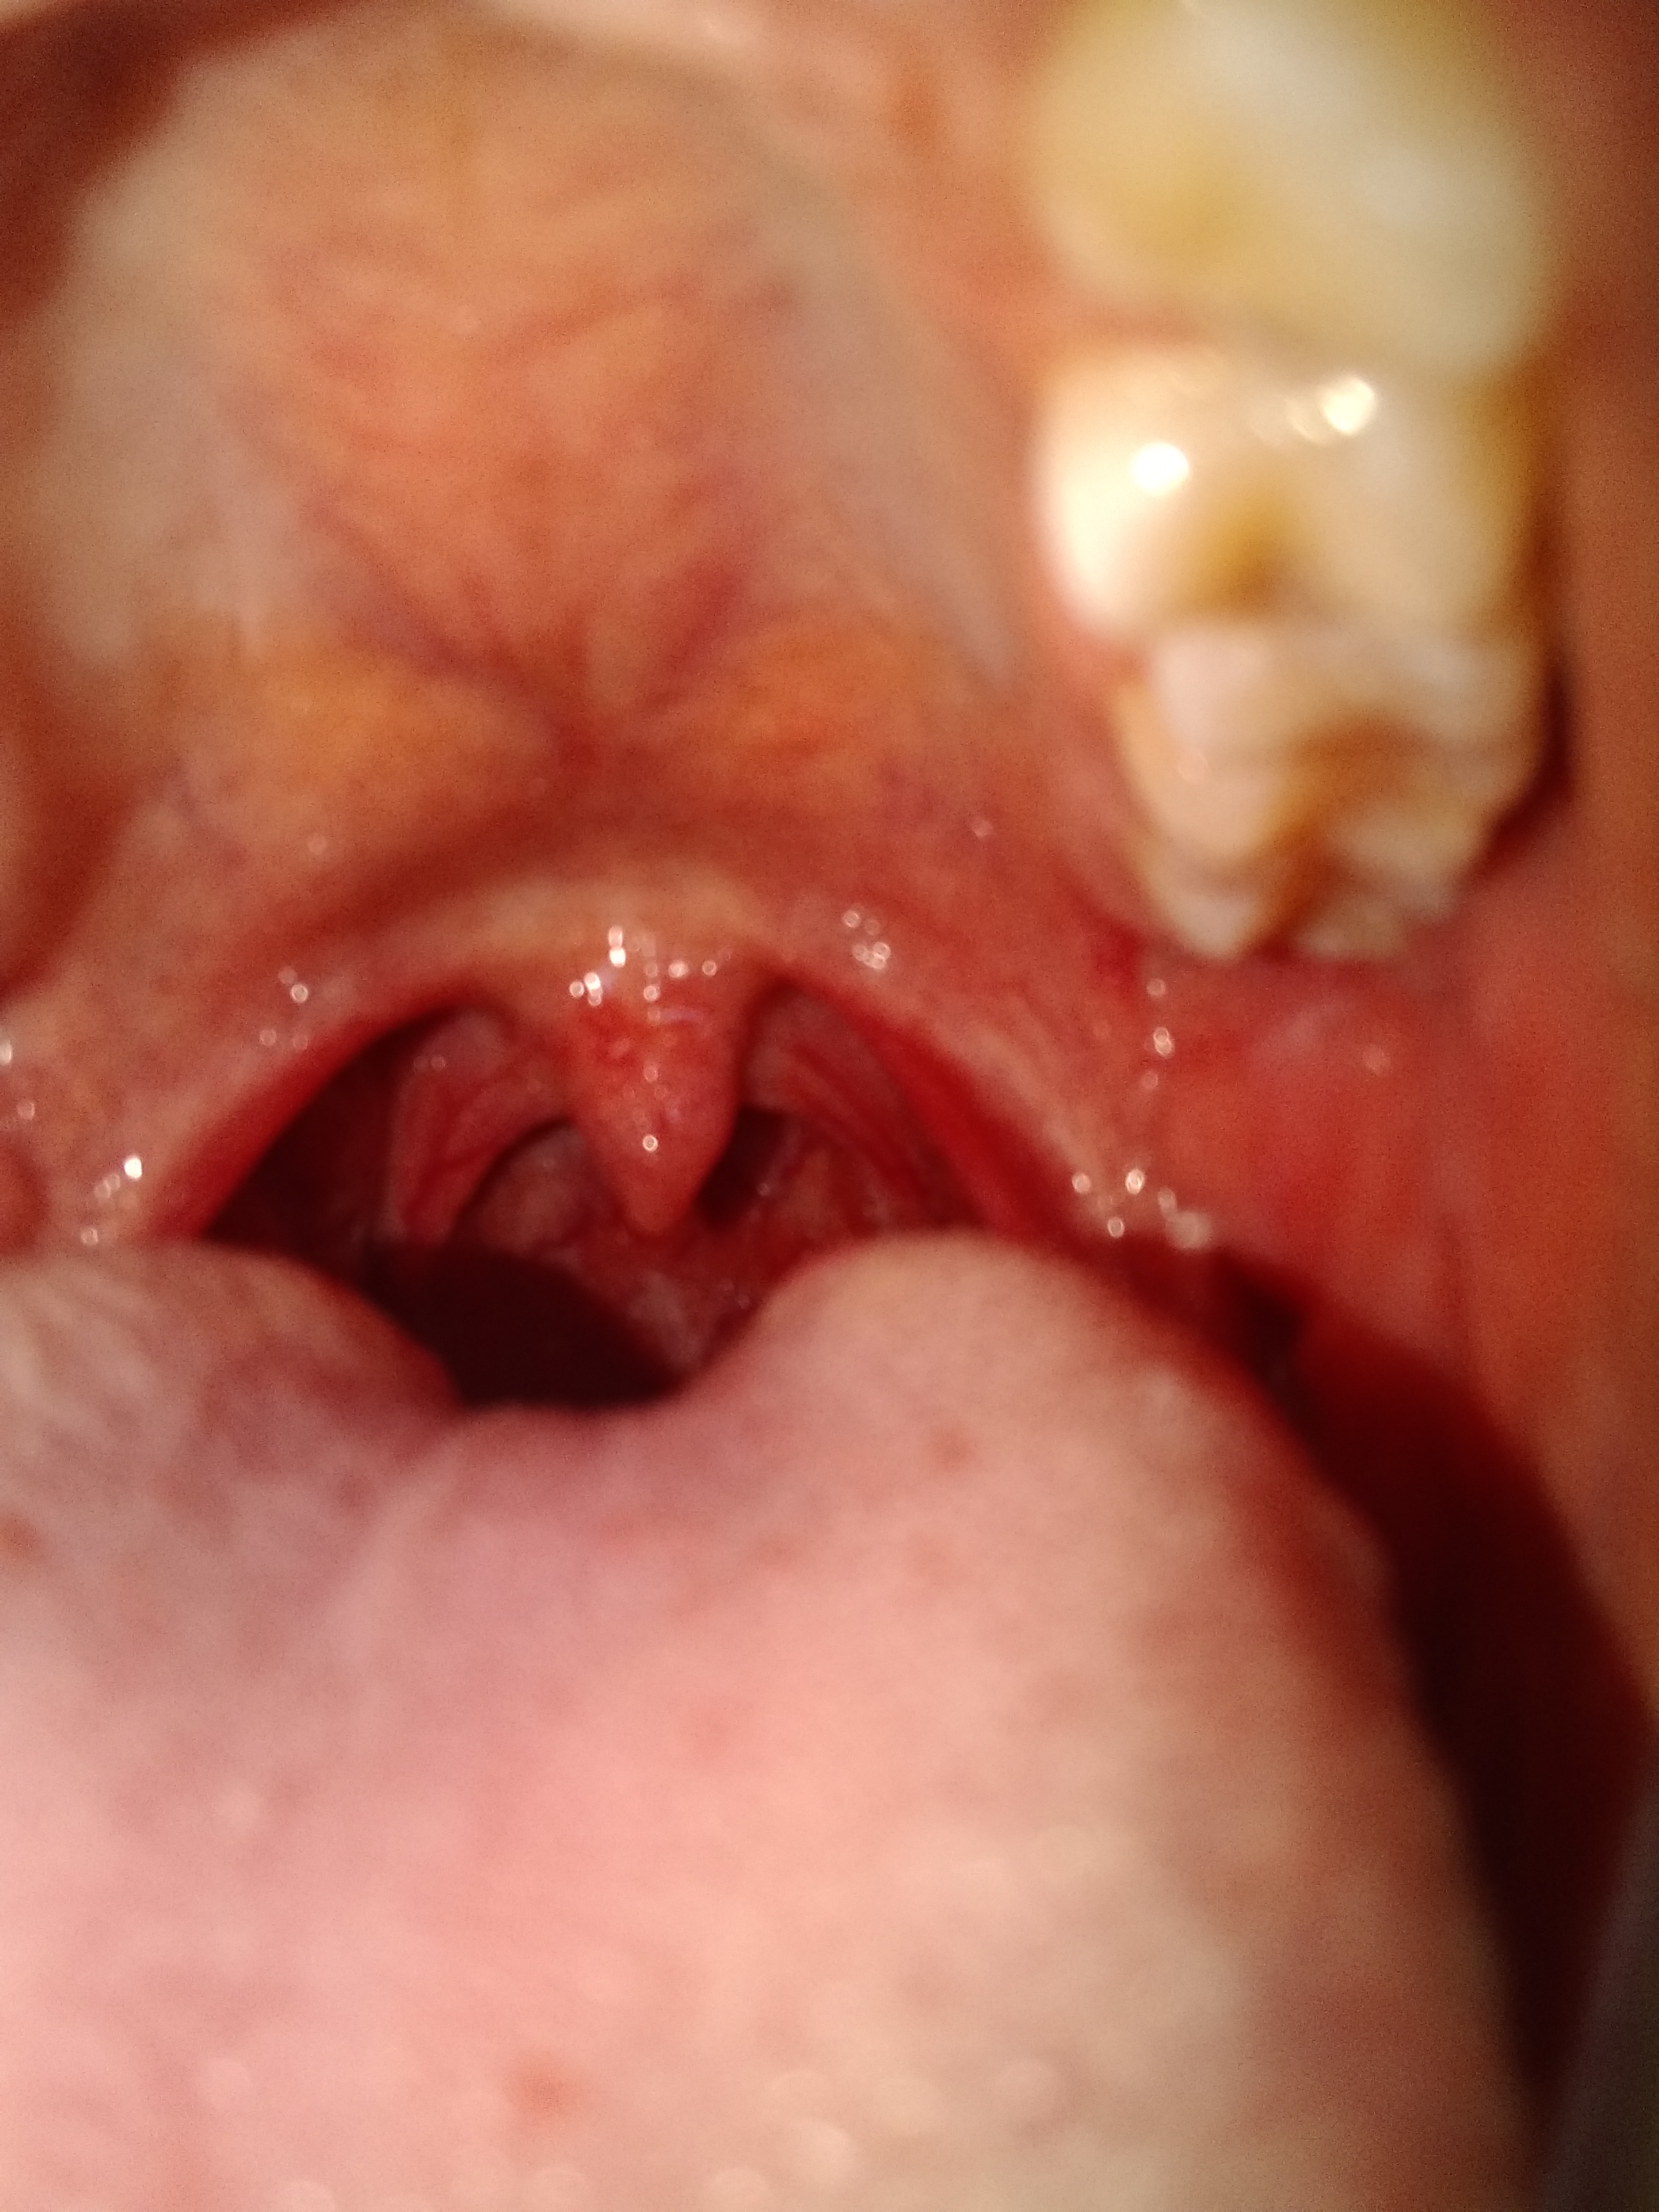

Tuve sexo oral homosexual pero al día siguiente amanecí con ruidos intestinales fuertes, de ahí molestias en la garganta, note que me salieron como puntos rojos en la garganta estoy un poco asustado

img_20200118_122828077.jpg

Alguien me puede orientar ? Ahora tengo como un punto negro en la ensia como con sangre